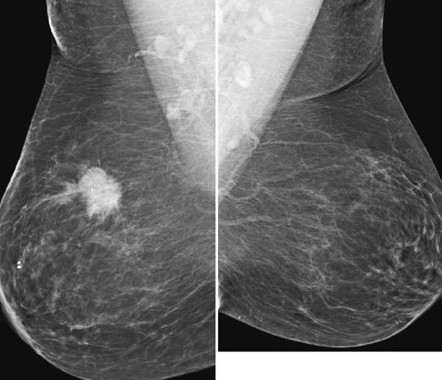

تصویر برداری ماموگرافی

ماموگرافی یکی از روش های تشخیص زودهنگام سرطان سینه است. ماموگرافی در آروین سنتر توسط مجهزترین دستگاه ها زیرنظر مجر ترین متخصصین انجام میگیرد.